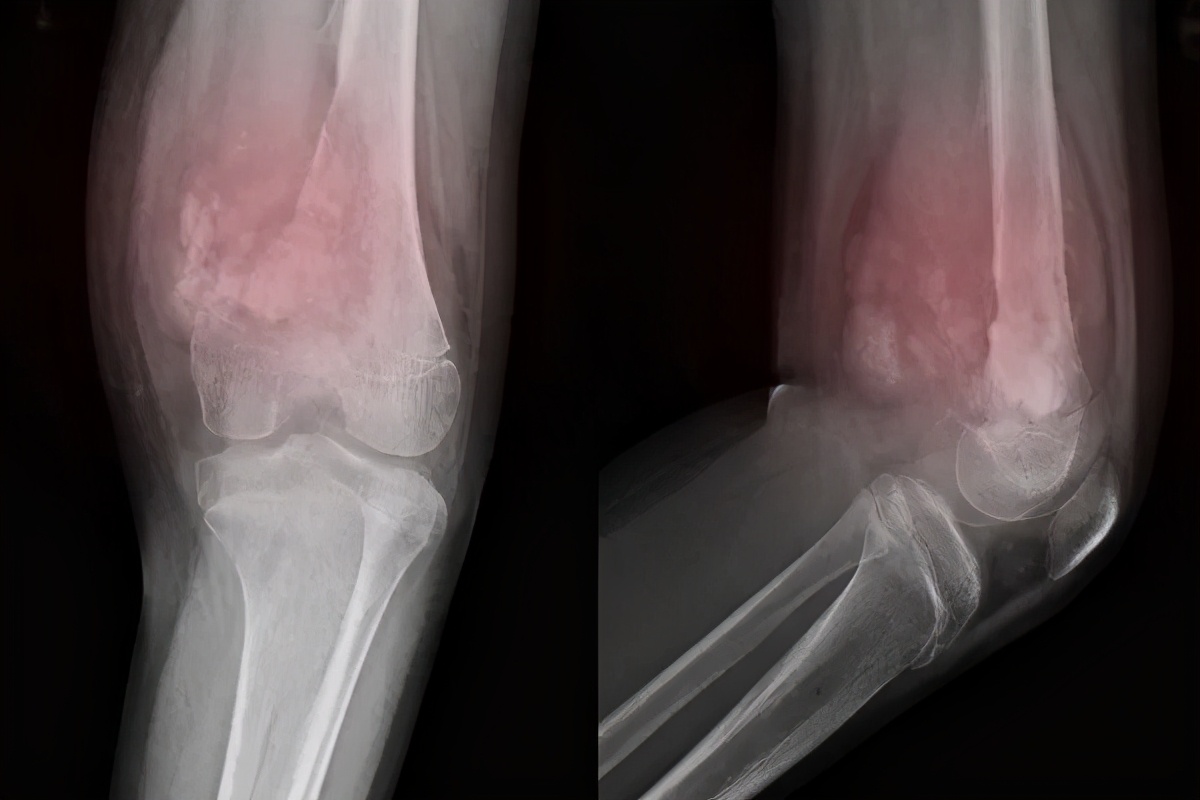

骨质疏松、骨关节炎、肿瘤骨转移等骨代谢异常相关疾病,多伴急、慢性疼痛,严重影响患者生活质量,随着我国医疗卫生水平的提高及人口平均寿命的延长,此类慢性疼痛病相关的社会问题和经济负担向我国的公共卫生系统提出了新的严峻挑战。

成骨破骨细胞功能的改变、骨及其附属组织(如软骨、滑囊等)微结构和微环境的改变均可导致骨代谢调节功能的紊乱,引起局部或整体骨代谢的异常。我们平常所说的骨质疏松、骨关节炎、肿瘤骨转移等都包含在内。